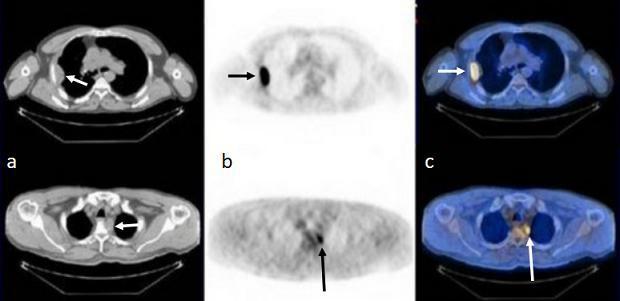

a.CT图像,组织结构显示清晰;b.PET图像,病灶显示敏感(箭);c.PET/CT融合图像